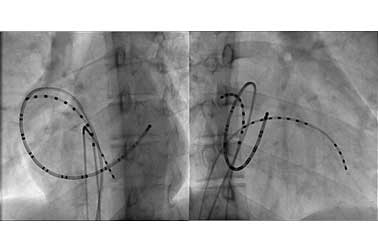

- 부정맥의 여러종류 가운데 약물 치료가 효과적이지 못하고, 근본적 치료가 어려운 경우 전극도자 절제술을 이용하여 치료합니다.

- 심장내에 여러 전극도자를 설치하고, 부정맥 발생 위치를 확인하고 전기적 에너지를 이용하여 심장 내 조직을 괴사시켜 치료를 합니다.

- 소아 환자에서는 주로 상심실성 빈맥, 심방 빈맥, 심실 빈맥 등의 환자에 시술이 이루어 지고 있습니다.

심장내 전극도자

심장내 심전도

방실 회귀성 빈맥환자에서의 전극도자 절제술